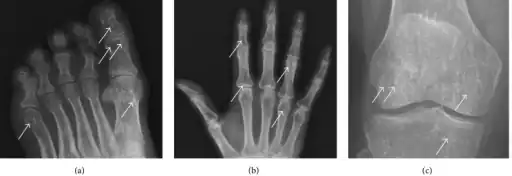

The radiographic appearance of osteopoikilosis on an X-ray is characterized by a pattern of numerous white densities of similar size spread throughout all the bones. This is a systemic condition. It must be differentiated from blastic metastasis, which can also present radiographically as white densities interspersed throughout bone. Blastic metastasis tends to present with larger and more irregular densities in less of a uniform pattern. Another differentiating factor is age, with blastic metastasis mostly affecting older people, and osteopoikilosis being found in people 20 years of age and younger.

The distribution is variable, though it does not tend to affect the ribs, spine, or skull.[3]

a-c)Osteopoikilosis in feet, hand, knee